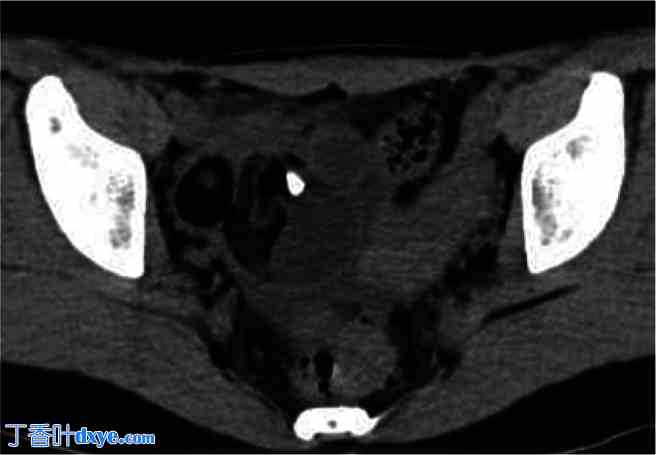

腹腔镜手术中的右侧卵巢畸胎瘤。

腹腔镜检查发现右侧卵巢畸胎瘤,并伴有黄色浑浊腹水。右侧附件未扭转或破裂。